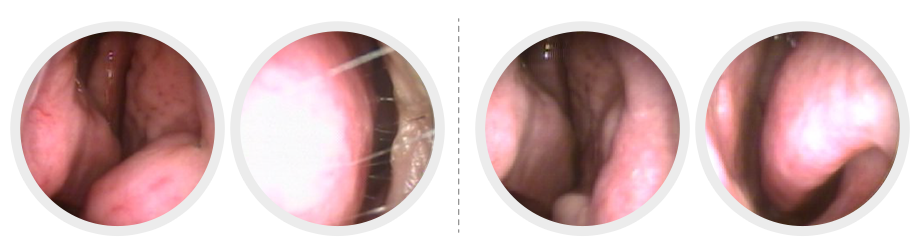

고주파비염수술 설명 1

고주파비염수술 설명 2 고주파비염수술 전 고주파비염수술 후